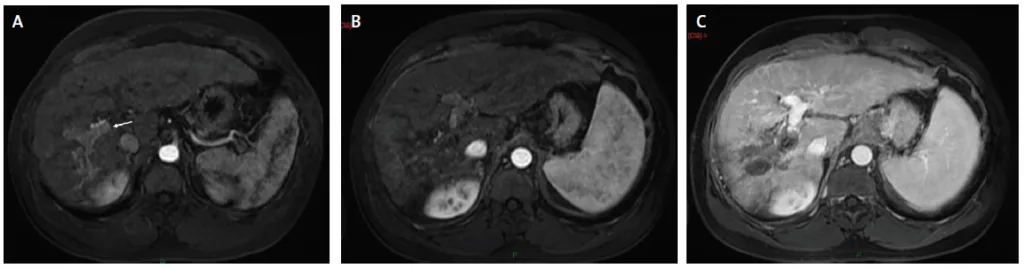

Figure 2. Ablation radiofréquence multibipolaire d’un CHC infiltrant du foie droit s’accompagnant d’une invasion postale Vp2

A. IRM axiale au temps artériel de l’injection de gadolinium montrant une tumeur mal limitée à cheval sur les segments 8 et 5. Il existe une invasion de la branche portale sectorielle antérieure droite (flèche).

B. Même coupe qu’en A sur laquelle le planning du positionnement des six électrodes est figuré (elles ne seront pas toutes positionnées dans le même plan. Les électrodes hors plan sont figurées en transparence). La stratégie du positionnement consiste à « couvrir » le secteur infiltré en positionnant les électrodes selon le grand axe de l’axe portal envahi.

C. Tomodensitométrie de contrôle un mois après au temps artériel de l’injection intraveineuse de produit de contraste iodée. La zone d’ablation a bien la forme pyramidale souhaitée avec pour sommet l’axe portale envahi et pour base le plan capsulaire des segments 8 et 5.